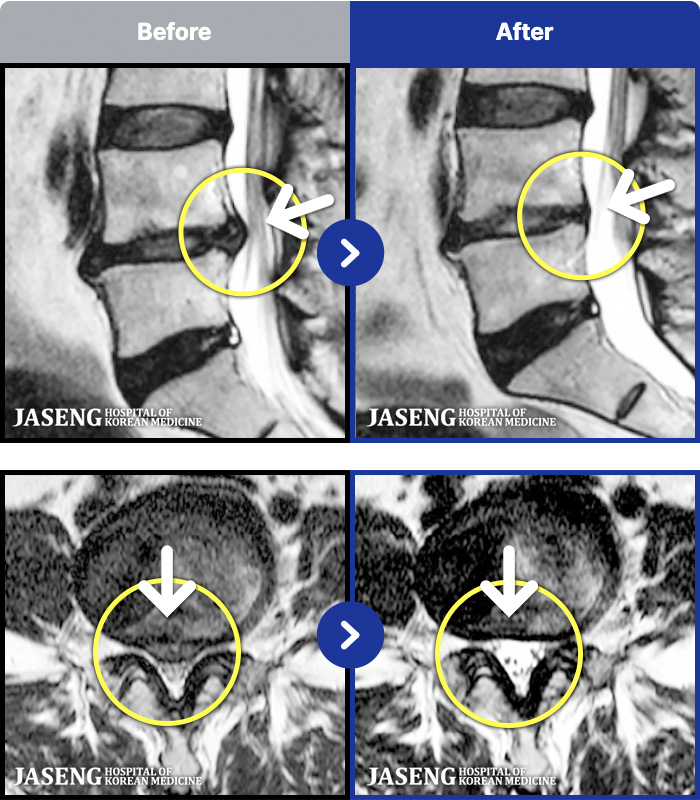

1,299 MRI ũ ʸ Ȯϼ.

[] 23.11.11~25.06.04